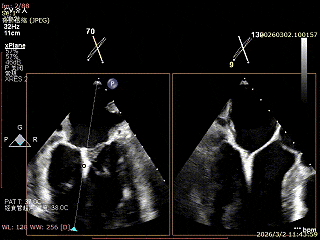

患者为房间隔缺损术后合并功能性二尖瓣反流(FMR),病变位于二尖瓣2区偏3区,因既往ASD修补史(可降解房间隔缺损封堵器),致房间隔穿刺区域存在瘢痕粘连、穿刺难度增加,于靠下靠后位置穿刺,避开房间隔缺损封堵伞,其余病变解剖结构相对简单;术前制定手术策略,拟使用1把XTR行二尖瓣修复,术中克服瘢痕粘连难点成功完成房间隔穿刺,穿刺点距二尖瓣瓣环平面3.1cm,将XTR‑CDS送入左心房,通过”A”旋钮旋转180度借高度,LVOT切面夹子严重Huge,使用”+”旋钮一键消除Huge,通过操控“M”旋钮将二尖瓣夹精准定位于2区正上方,完成弹道测试及Orientation调整后,于2区将夹子送入左心室,顺利捕捞并夹持瓣叶后缓慢闭合夹臂;TEE检查示二尖瓣反流充分降低至微量,二尖瓣双孔组织桥稳定,跨瓣压差2mmHg,肺静脉逆流明显改善,手术安全顺利结束。

房间隔成功穿刺,穿刺位点距二尖瓣瓣环平面高度3.1cm,可使用高度不足

3D enface 切面

3D enface观察反流